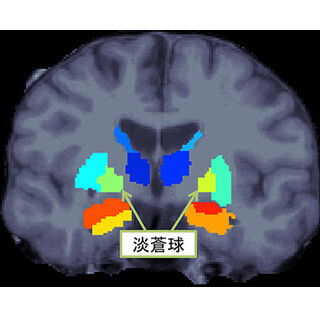

大阪大学(阪大)と東京大学(東大)は1月19日、統合失調症では淡蒼球という脳領域の体積に左右差があることを発見したと発表した。

淡蒼球は大脳皮質下領域にある大脳基底核の1つで、運動機能や、動機付け、意欲、欲求が満たされる感覚に関与するとされる。統合失調症患者では健常者に比べて体積が大きいことが知られていた。

今回の研究は認知ゲノム共同研究機構(COCORO)に参加する11の研究機関から収集した1680名の健常者と884名の統合失調症患者のMRI脳構造画像を比較解析し、統合失調症における大脳皮質下領域構造の体積やその左右差の変化を調べた。その結果、健常者では視床、側脳室、尾状核、被殻では左側優位、海馬、扁桃体で右側優位であり、淡蒼球、側坐核では非対称性が認められなかった。この傾向は統合失調症患者でもほぼ同様だったが、淡蒼球体積は右側に比べて左側が大きいことがわかった。